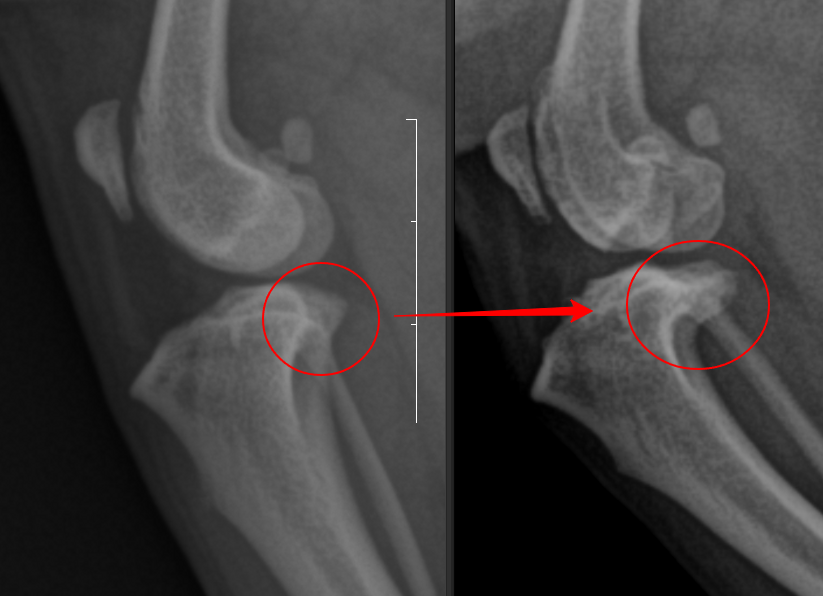

수술을 한 좌측 다리에서는 경미한 경골 조 면부 enthesophytosis가 관찰된다. 반면 수술하지 않은 우측 다리의 경우는 완전히 다른 예후를 보인다.

관절낭종창이나 관절의 심한 퇴행성 변화 양상은 차치하더라도 경골 조면의 후방의 골 증식양상이 뚜렷하며 이로서 경골의 TPL이 증가한 양상이 관찰된다. 이렇게 되면 십자인대에 가해지는 압력의 크기가 증가하여 십자인대가 파열할 가능성이 높으며 그 증거가 관절낭의 종창이다.

향후 십자인대의 파열 가능성이 매우 높아지게 진행된다.